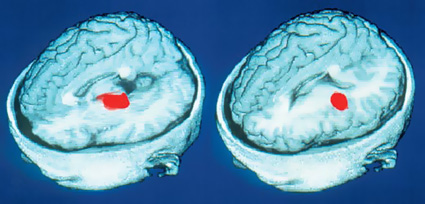

Отождествлять ли разум человека с мозгом, верить ли в участие в процессе мышления тонких материй или нет вопрос отдельный и для каждого сугубо индивидуальный, но не зависимо от убеждений можно беспорно констатировать, что мозг является вычислительным инструментом мышления. При поражении отдельных его участков человек теряет связанные с этим участком способности в произвение соответсвенной умственной работы: распознавание лиц, чтение, анализ и т.д. Соответсвие умственной деятельности различным участкам можно наблюдать на специальных приборах защет электрохимической природый нейронных сигрналов.

Участки мозга (красные), связанные со словестным обучением. Слева — участок, отвечающий за запоминание самого слова, справа — за сохранение в памяти его значения